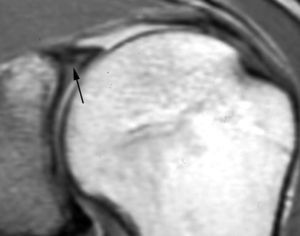

Lesión de Perthes

La lesión de Perthes es similar a la de Bankart, con la excepción de que no existe rotura capsuloperióstica, aunque el periostio puede estar separado del borde anterior del margen glenoideo (fig. 10). Esta lesión puede ser difícil de visualizar, incluso con artrorresonancia, a menos que se obtengan imágenes con la posición de abducción y rotación externa (ABER). En un estudio de 10 casos, verificados quirúrgicamente, Wisher et al17 comprobaron que el 50% de las lesiones de Perthes sólo podían visualizarse en la posición de ABER.

Fig. 10.--Lesión de Perthes. Artrorresonancia T1 con saturación grasa en posición ABER (abducción y rotación externa), donde se observa un arrancamiento parcial del labio glenoideo (flecha) con conservación de la unión capsuloperióstica.